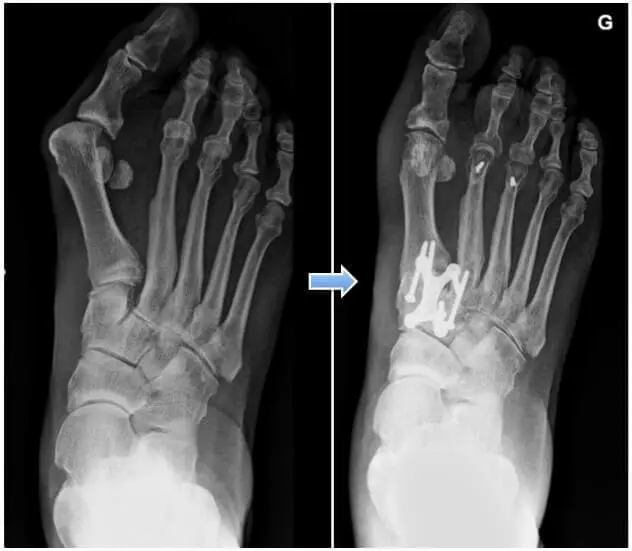

L’arthrodèse est indiquée lors de désaxations majeures ou arthrosiques. Le mode de fixation interdit souvent l’appui pendant 6 semaines ou éventuellement un plâtre de protection.

En cas de mobilité réduite, de faible réductibilité, d’hallux valgus avec arthrose, l’arthrodèse reste pour nous une des meilleures solutions.